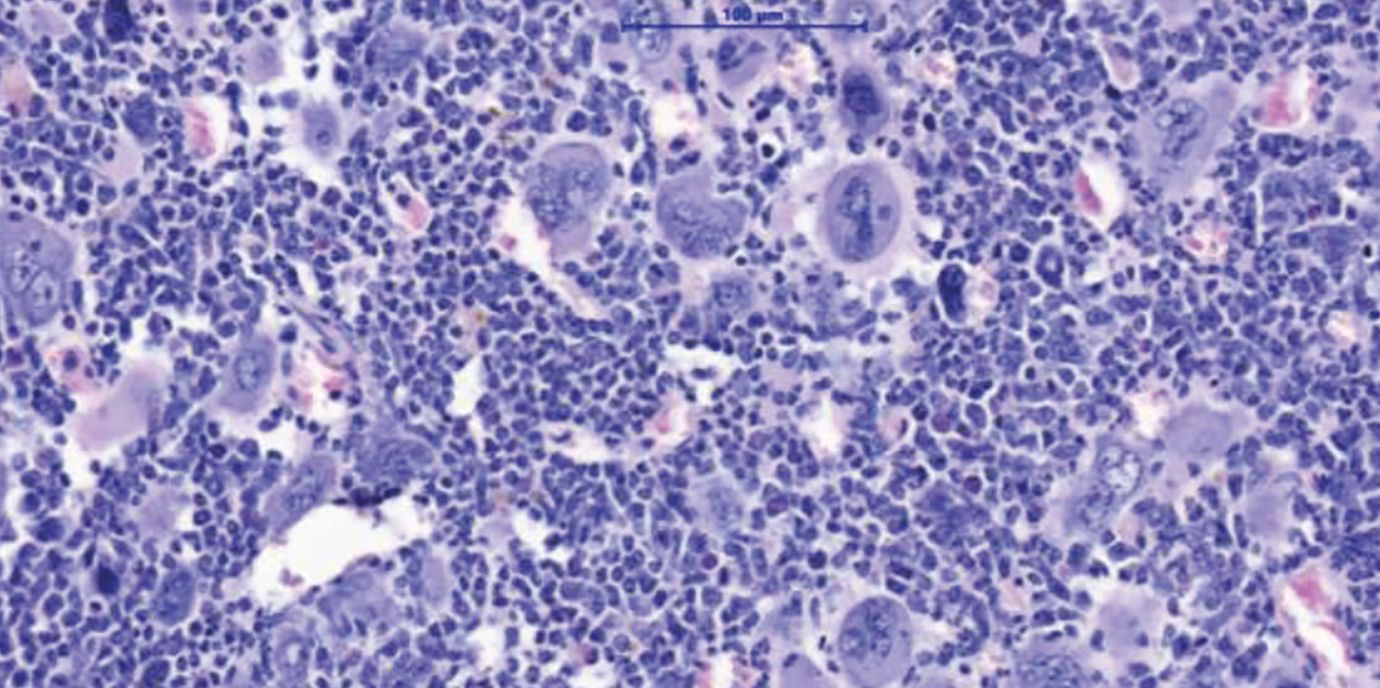

Myeloproliferative Neoplasien (MPN) sind Blutkrebserkrankungen, die durch eine Überproduktion von Blutzellen gekennzeichnet ist. Diese Erkrankungen treten in der Regel ab einem Alter von 60+ Jahren auf und können über lange Zeit gut kontrolliert werden. Gefährlich werden MPN vor allem nach dem Übergang in eine Myelofibrose – eine lebensbedrohliche Vernarbung des Knochenmarks. Eine allogene Stammzelltransplantation bietet für die betroffenen Patient:innen bis heute die einzige Aussicht auf Heilung. „Wir brauchen dringend neue Therapiekonzepte. Eine Stammzell-Transplantation ist für viele Patient:innen aufgrund ihres hohen Alters oder wegen Begleiterkrankungen mit zu hohen Risiken verbunden“, erklärt Dominik Wolf, Direktor der Univ.-Klinik für Innere Medizin V (Hämatologie und Onkologie) an der Medizinischen Universität Innsbruck, den Hintergrund einer soeben im Fachjournal Nature Communications hochrangig publizierten Forschungsarbeit, die er konzipiert und gemeinsam mit Lino Teichman und Miriam Körber vom UKBonn durchgeführt hat. „Wir zeigen in dieser Arbeit ein mögliches neues Therapiekonzept auf, das man klinisch weiterentwickeln sollte“, sagt Wolf, der gemeinsam mit Lino Teichmann als Letzt- und korrespondierender Autor firmiert. Den Wissenschafter:innen ist es gelungen, das NLRP3-Inflammason im Tiermodell zu hemmen und dadurch deutliche Verbesserungen des Krankheitsverlaufs zu erzielen: Die Knochenmarksvernarbung und die Milzvergrößerung bildeten sich zurück und das Blutbild verbesserte sich.

Konkret haben sich die Autor:innen mit den Mechanismen der Entzündungsreaktion bei MPN beschäftigt, da diese zu vielen klinischen Symptomen und letztlich auch zur Vernarbung des Knochenmarks führt. Das NLRP3-Inflammasom ist ein Sensor für Gefahrensignale, der Entzündungsprozesse im Körper steuert und dessen Bedeutung bereits eingehend bei chronischen Entzündungserkrankungen wie Atherosklerose, Gicht oder auch Diabetes Typ-2 studiert wurde. Bei MPN wird die Entzündung in den bösartigen, aber auch in den begleitenden, noch gesunden Blutzellen von einer genetischen Treibermutation ausgelöst, wobei hier die aktivierende Mutation JAK2V617F eine zentrale Rolle spielt.

„Wir haben uns erstmalig damit beschäftigt, welche funktionelle Rolle das NLRP3-Inflammasom für die Entzündungsreaktion bei myeloproliferativen Neoplasien hat“, sagt Erstautorin Ruth-Miriam Körber vom Universitätsklinikum Bonn. Dafür haben die Mediziner:innen in Zusammenarbeit mit der German Study Group of MPN (GSG-MPN) eine große Anzahl von Proben ausgewertet und die Entzündungsreaktionen kartiert, bevor sie anhand unterschiedlicher Techniken die Aktivierung des NLRP3-Inflammasoms bei den Patient:innen und auch im MPN-Tiermodell nachweisen konnten.

„Wir haben eng mit Eicke Latz, dem Leiter des Deutschen Rheuma-Forschungszentrums in Berlin, kooperiert, der uns verschiedenste Tools zur Verfügung gestellt hat. Damit konnten wir zeigen, dass diese Entzündungsfaktoren wirklich in Abhängigkeit von NLRP3 produziert werden. Besonders interessant war, dass wir das NLRP3 genetisch in Knockout-Mäusen und auch mithilfe eines neuartigen und spezifischen NLRP3-inhibierenden Medikaments hemmen konnten“, spricht Wolf einen möglichen Therapieansatz an. Dank IFM-2384, einer Substanz, die ebenfalls von Eicke Latz bereitgestellt wurde, konnte im Tiermodell eine deutliche Verbesserung erzielt werden. „Die Knochenmarksvernarbungen und auch die meistens sehr ausgeprägten Milzvergrößerungen gingen zurück. Wir konnten auch das Blutbild verbessern“, zählt Wolf auf.